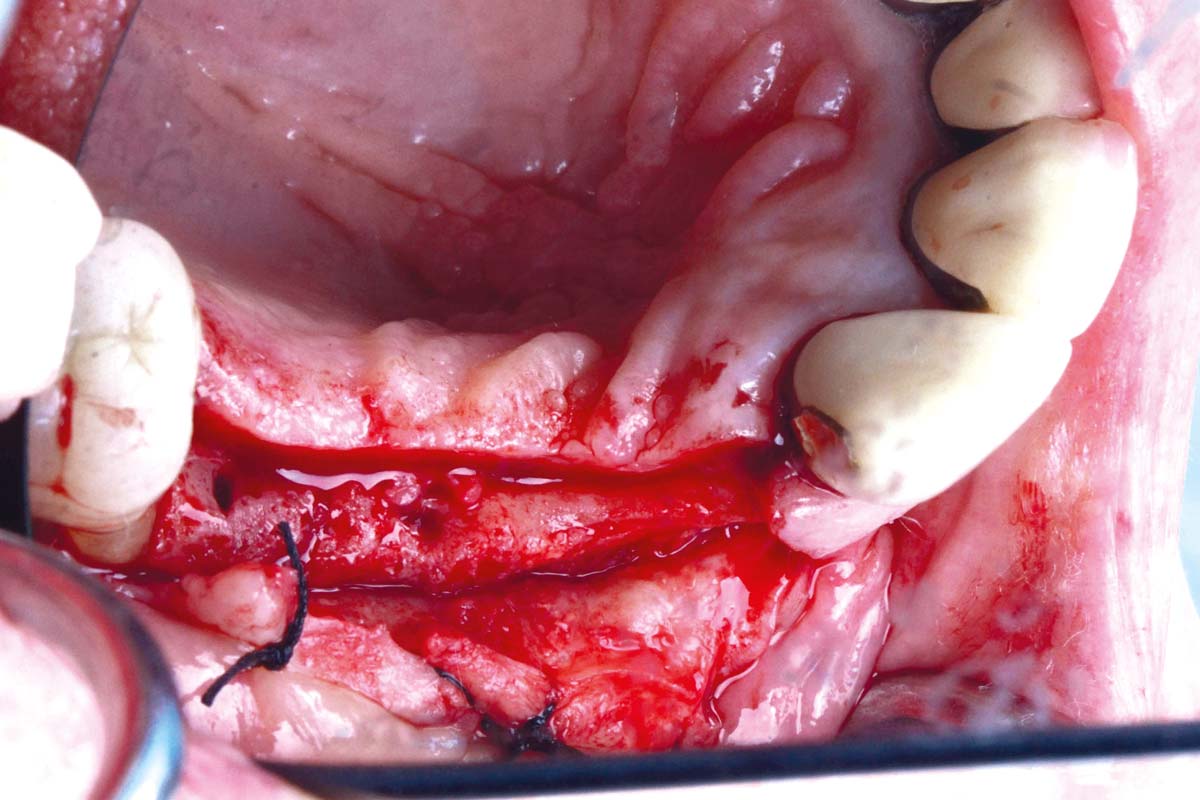

Ridge augmentation in the mandible with maxgraft® bonebuilder– Dr. R. Morger

Initial clinical situation: Free end situation in quadrant three and four